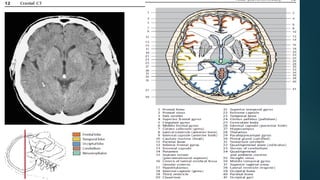

Este documento es el programa para un taller de imágenes del curso de emergencia 2015 impartido por el Dr. Víctor Delgado. El taller se centra en el uso de imágenes médicas para el diagnóstico y tratamiento de pacientes en coma traumático según la base de datos de Marshall. El Dr. Delgado es el único instructor repetido a lo largo del documento.